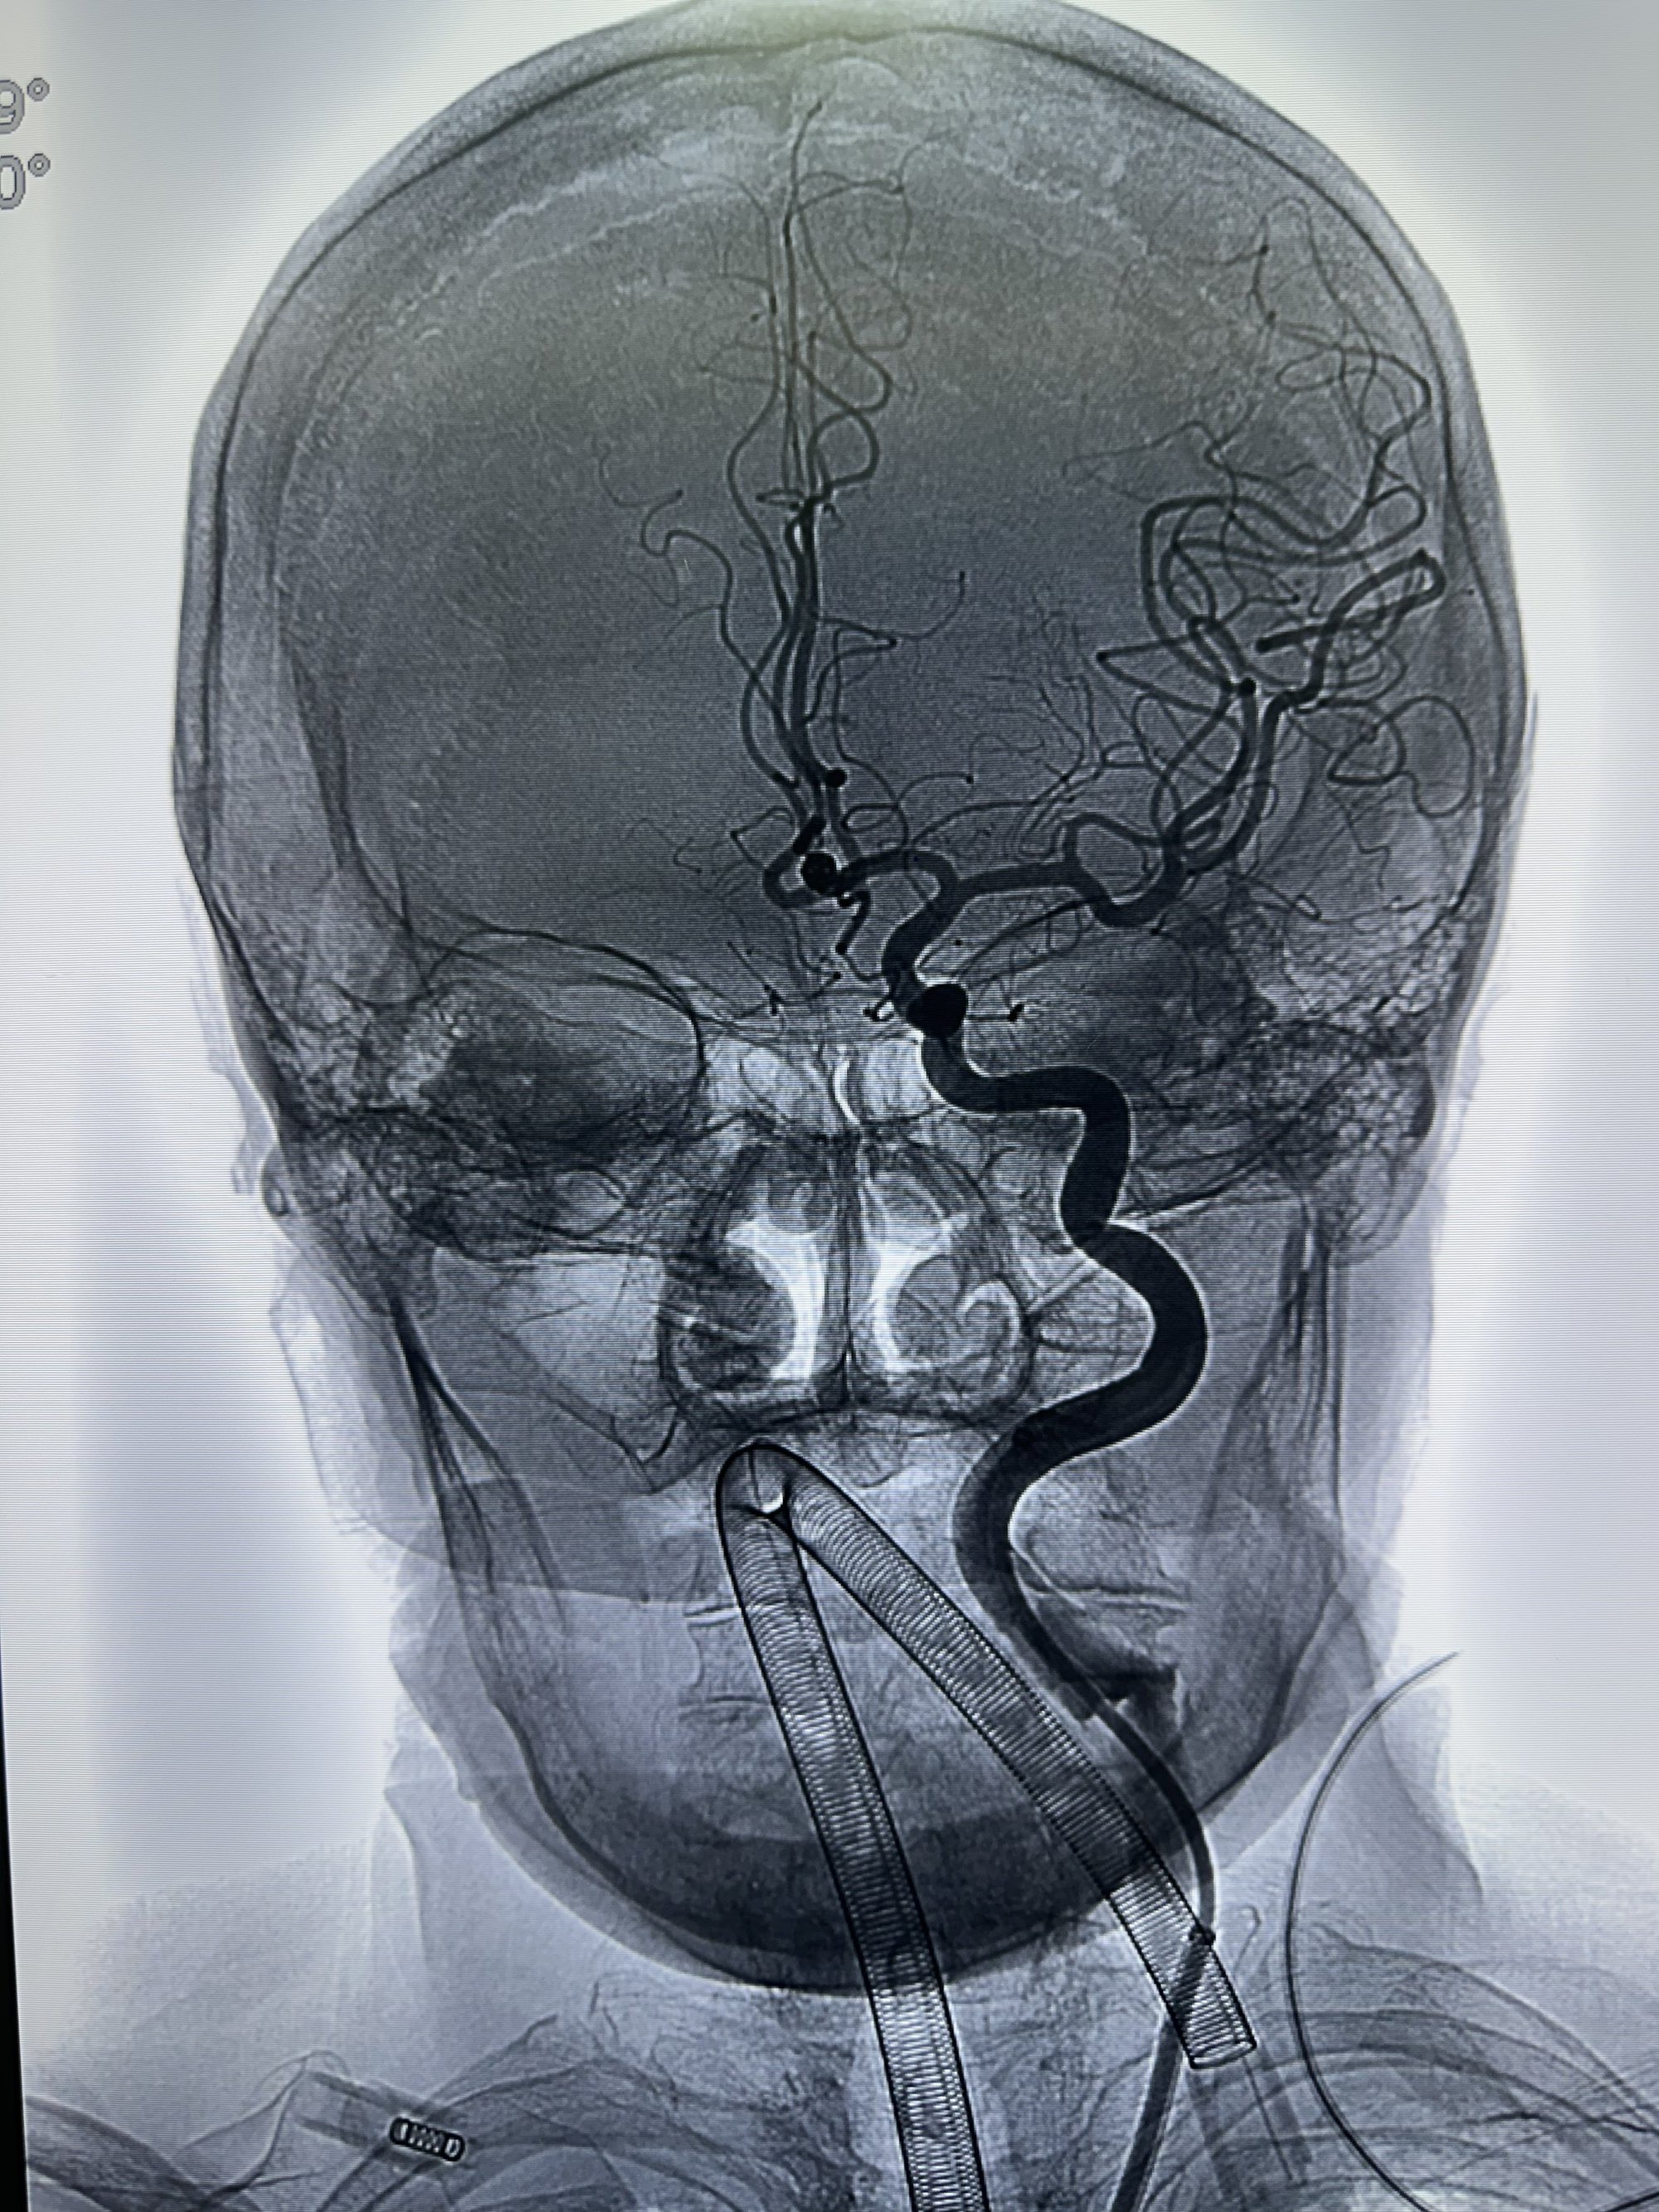

右侧颈内动脉造影

工作角度,选择Neuromax90加上6f的银蛇115